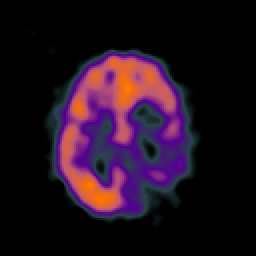

SPECT TC Study #4 -- Slice #37

[Home][Help][Clinical][Tour 1][Tour 2][Tour 3] Slice 37